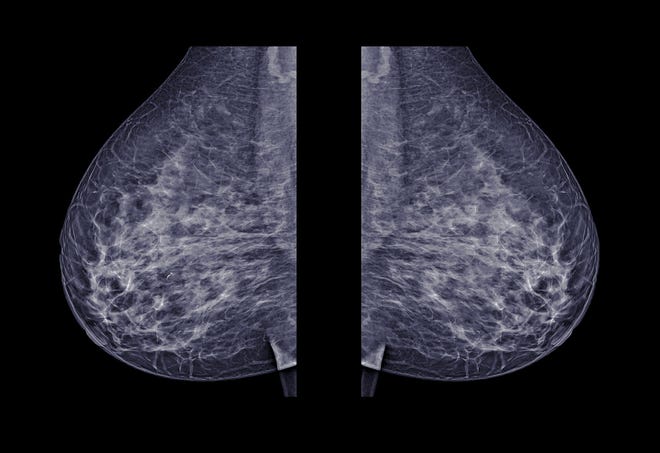

3d Mammogram Dense Breast

3d mammogram dense breast. A radiologist can determine if a woman has dense breasts using a mammogram. A 3d mammogram provides an image of the breast from multiple layers angles or slices which makes finding abnormalities lumps or tumors easier. A 3d mammogram offers advantages in detecting breast cancer in people with dense breast tissue because the 3d image allows doctors to see beyond areas of density. 3d mammograms can be especially useful for those with dense breast tissue.

Traditionally these images have been taken in 2 d so theyre flat black and white pictures that a healthcare. A digital mammogram provides a 2 dimensional picture of the breast which is a 3 dimensional object. Helpful for dense tissue 3d mammography also called digital breast tomosynthesis is a relatively new technology. Dense breasts can make it even more difficult to find cancer on a traditional mammogram as dense tissue may hide a tumor from view.

This type of screening is similar to mammography in that the breast is compressed and x rays are used to generate an image. The breast is composed of different structures such as milk ducts fat connective tissues and blood vessels. A study has found that adding 3 d mammography also called digital tomosynthesis or breast ultrasound to regular screening mammograms can detect more cancers in dense breasts. A mammogram is an x ray of breast tissue.

The primary benefit of 3d mammograms experts say is for women who have dense breasts. Breast tissue is composed of milk glands milk ducts and supportive tissue dense breast tissue and fatty tissue. These structures appear at different levels within the breasts and can overlap one another when viewed as a 2d image.